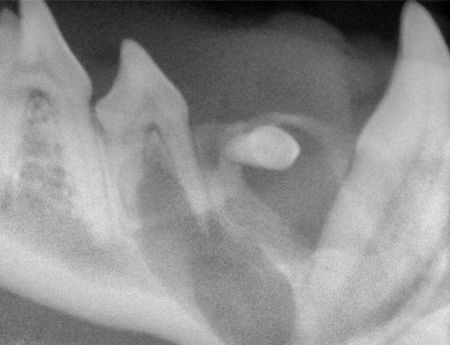

Quite unlike this patient with an obvious mass that led to detection, most dentigerous cysts do not produce clinical signs in their early stages. Dogs are particularly predisposed to dentigerous cysts, most commonly associated with an unerupted mandibular first premolar. Brachycephalic breeds appear to be overrepresented (Photo 7). Expansion is generally within the bone and not in the surrounding gingiva.

Photo 7: An unerupted first premolar has resulted in a cyst in this 3-year-old brachycephalic dog.